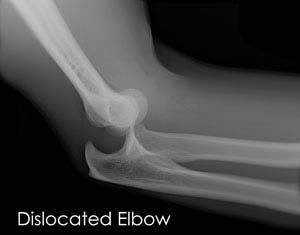

To diagnose elbow dislocation, your doctor will examine your arm. Your doctor will check the pulses at the wrist and evaluate the circulation to the arm. An X-ray is necessary to determine if there is a break in the bone. An arteriogram, an X-ray of your artery, can be helpful to determine if the artery is injured.